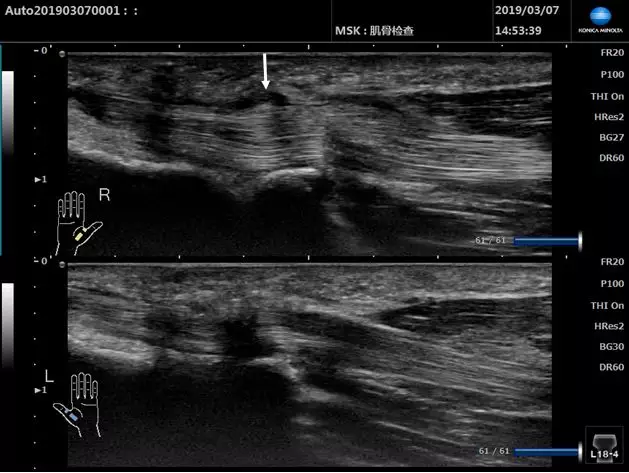

超聲下的姆長屈肌腱(長軸)

■ 上圖為患側,下圖為健側,患側肌腱增粗,A1滑車低回聲增厚(白色箭頭處)